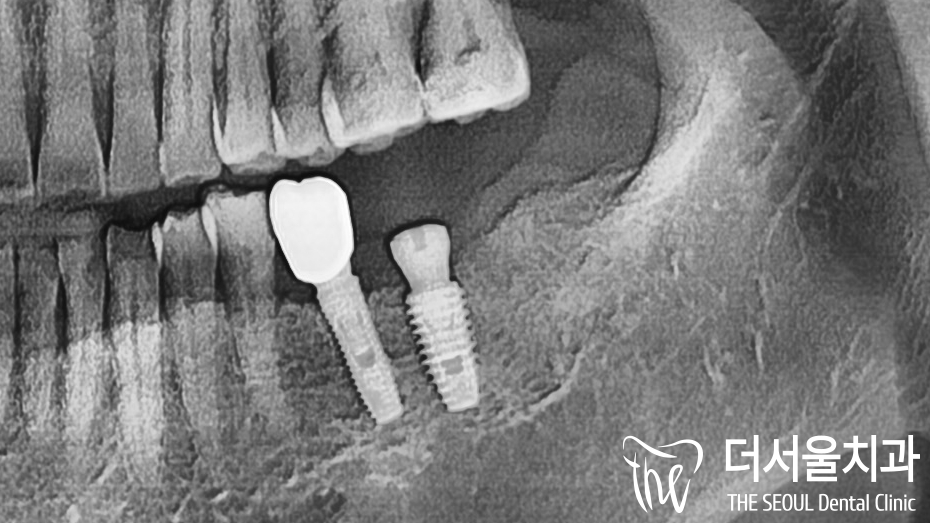

계획했던대로 발치를 진행했습니다.

염증이 나타나 있는 것은 맞지만

생각했던 것보다 심하진 않아서

따로 골이식을 동반할 필요는 없겠네요.

깨끗하게 발치를 마친 곳에

픽스쳐를 심어놓은 모습입니다.